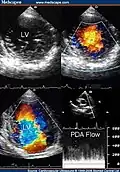

Trabeculation of the ventricles is normal, as are prominent, discrete muscular bundles greater than 2mm. In non-compaction there are excessively prominent trabeculations. Echocardiography is the reference standard for diagnosing NCC, although it can be well defined by computer tomography scan, positron emission tomography and magnetic resonance imaging.[13] Chin, et al., described echocardiographic method to distinguish non-compaction from normal trabeculation. They described a ratio of the distance from the trough and peak, of the trabeculations, to the epicardial surface.[14] Non-compaction is diagnosed when the trabeculations are more than twice the thickness of the underlying ventricular wall.

Transthoracic two-dimensional echocardiogram in apical four chamber and parasternal short axis at the level of both ventricles demonstrate dilatation, deep trabeculae and intertrabecular recesses in the inferior, lateral, anterior walls, middle and apical portions of the septum and apex of the left ventricle.